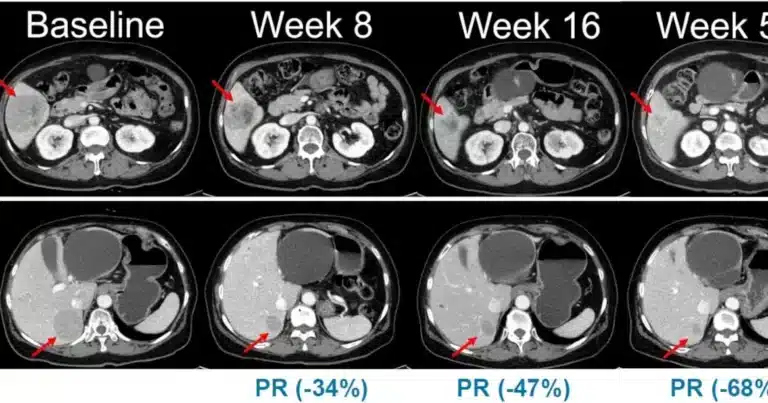

The Phase 2 study enrolls 45 patients to assess the efficacy and safety of Belvarafenib combined with the MEK inhibitor cobimetinib.

Hanmi Pharm officials stated, “The Belvarafenib and cobimetinib combination surpasses limitations of prior BRAF monotherapy and BRAF-MEK regimens, offering substantial clinical benefits to broader patient groups with genetic mutations.”